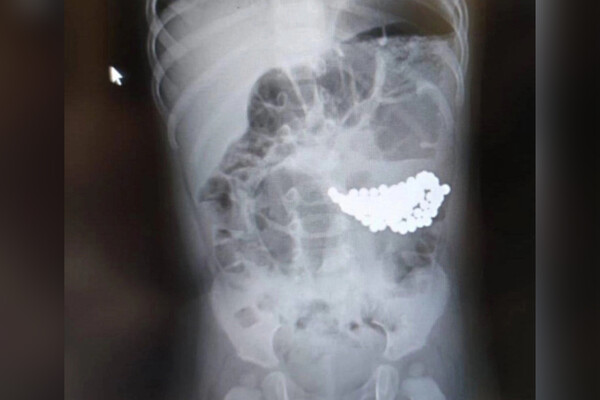

В Ямало-Ненецком автономном округе двухлетний мальчик проглотил 18 магнитов и не выжил. Об этом сообщает Telegram-канал «Реальный Ноябрьск».

По информации канала, инцидент произошел в поселке Пурпе. Родители двухлетнего ребенка обратились за медицинской помощью для сына сразу, как заметили пропажу магнитов-бусинок. При этом мальчик якобы вел себя, как обычно. Семья вызвала ребенку скорую, пострадавшего доставили в больницу. Медики оценили состояние дошкольника как тяжелое и начали необходимые реанимационные мероприятия, но спасти его не удалось.

До этого в Подмосковье спасли полуторагодовалого ребенка со 130 магнитами и батарейкой в желудке. Из-за скопления магнитов у пациента образовалась язва.